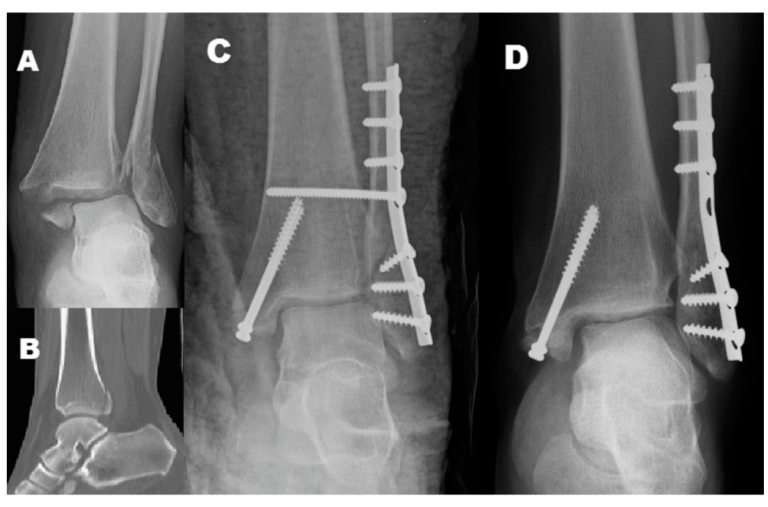

后踝骨折及下胫腓联合螺钉取出时机与下胫腓不稳的关系

对合并下胫腓联合损伤的内外踝骨折或三踝骨折,常规置入下胫腓螺钉,同时为避免螺钉断裂,恢复下胫腓微动,术者常规在术后6-8周或术后3月取下胫腓螺钉,但下胫腓螺钉取去存在下胫腓不稳风险。为研究双踝/三踝骨折下胫腓螺钉取出的最佳时机,及未固定的后踝与下胫腓稳定性的关系,有学者进行了相关研究,结果发表在近期Injury期刊上。